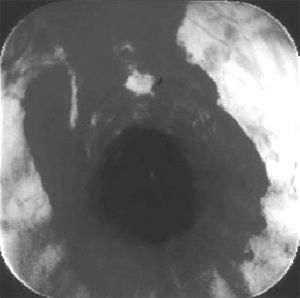

A new development in the diagnosis of upper airway disease